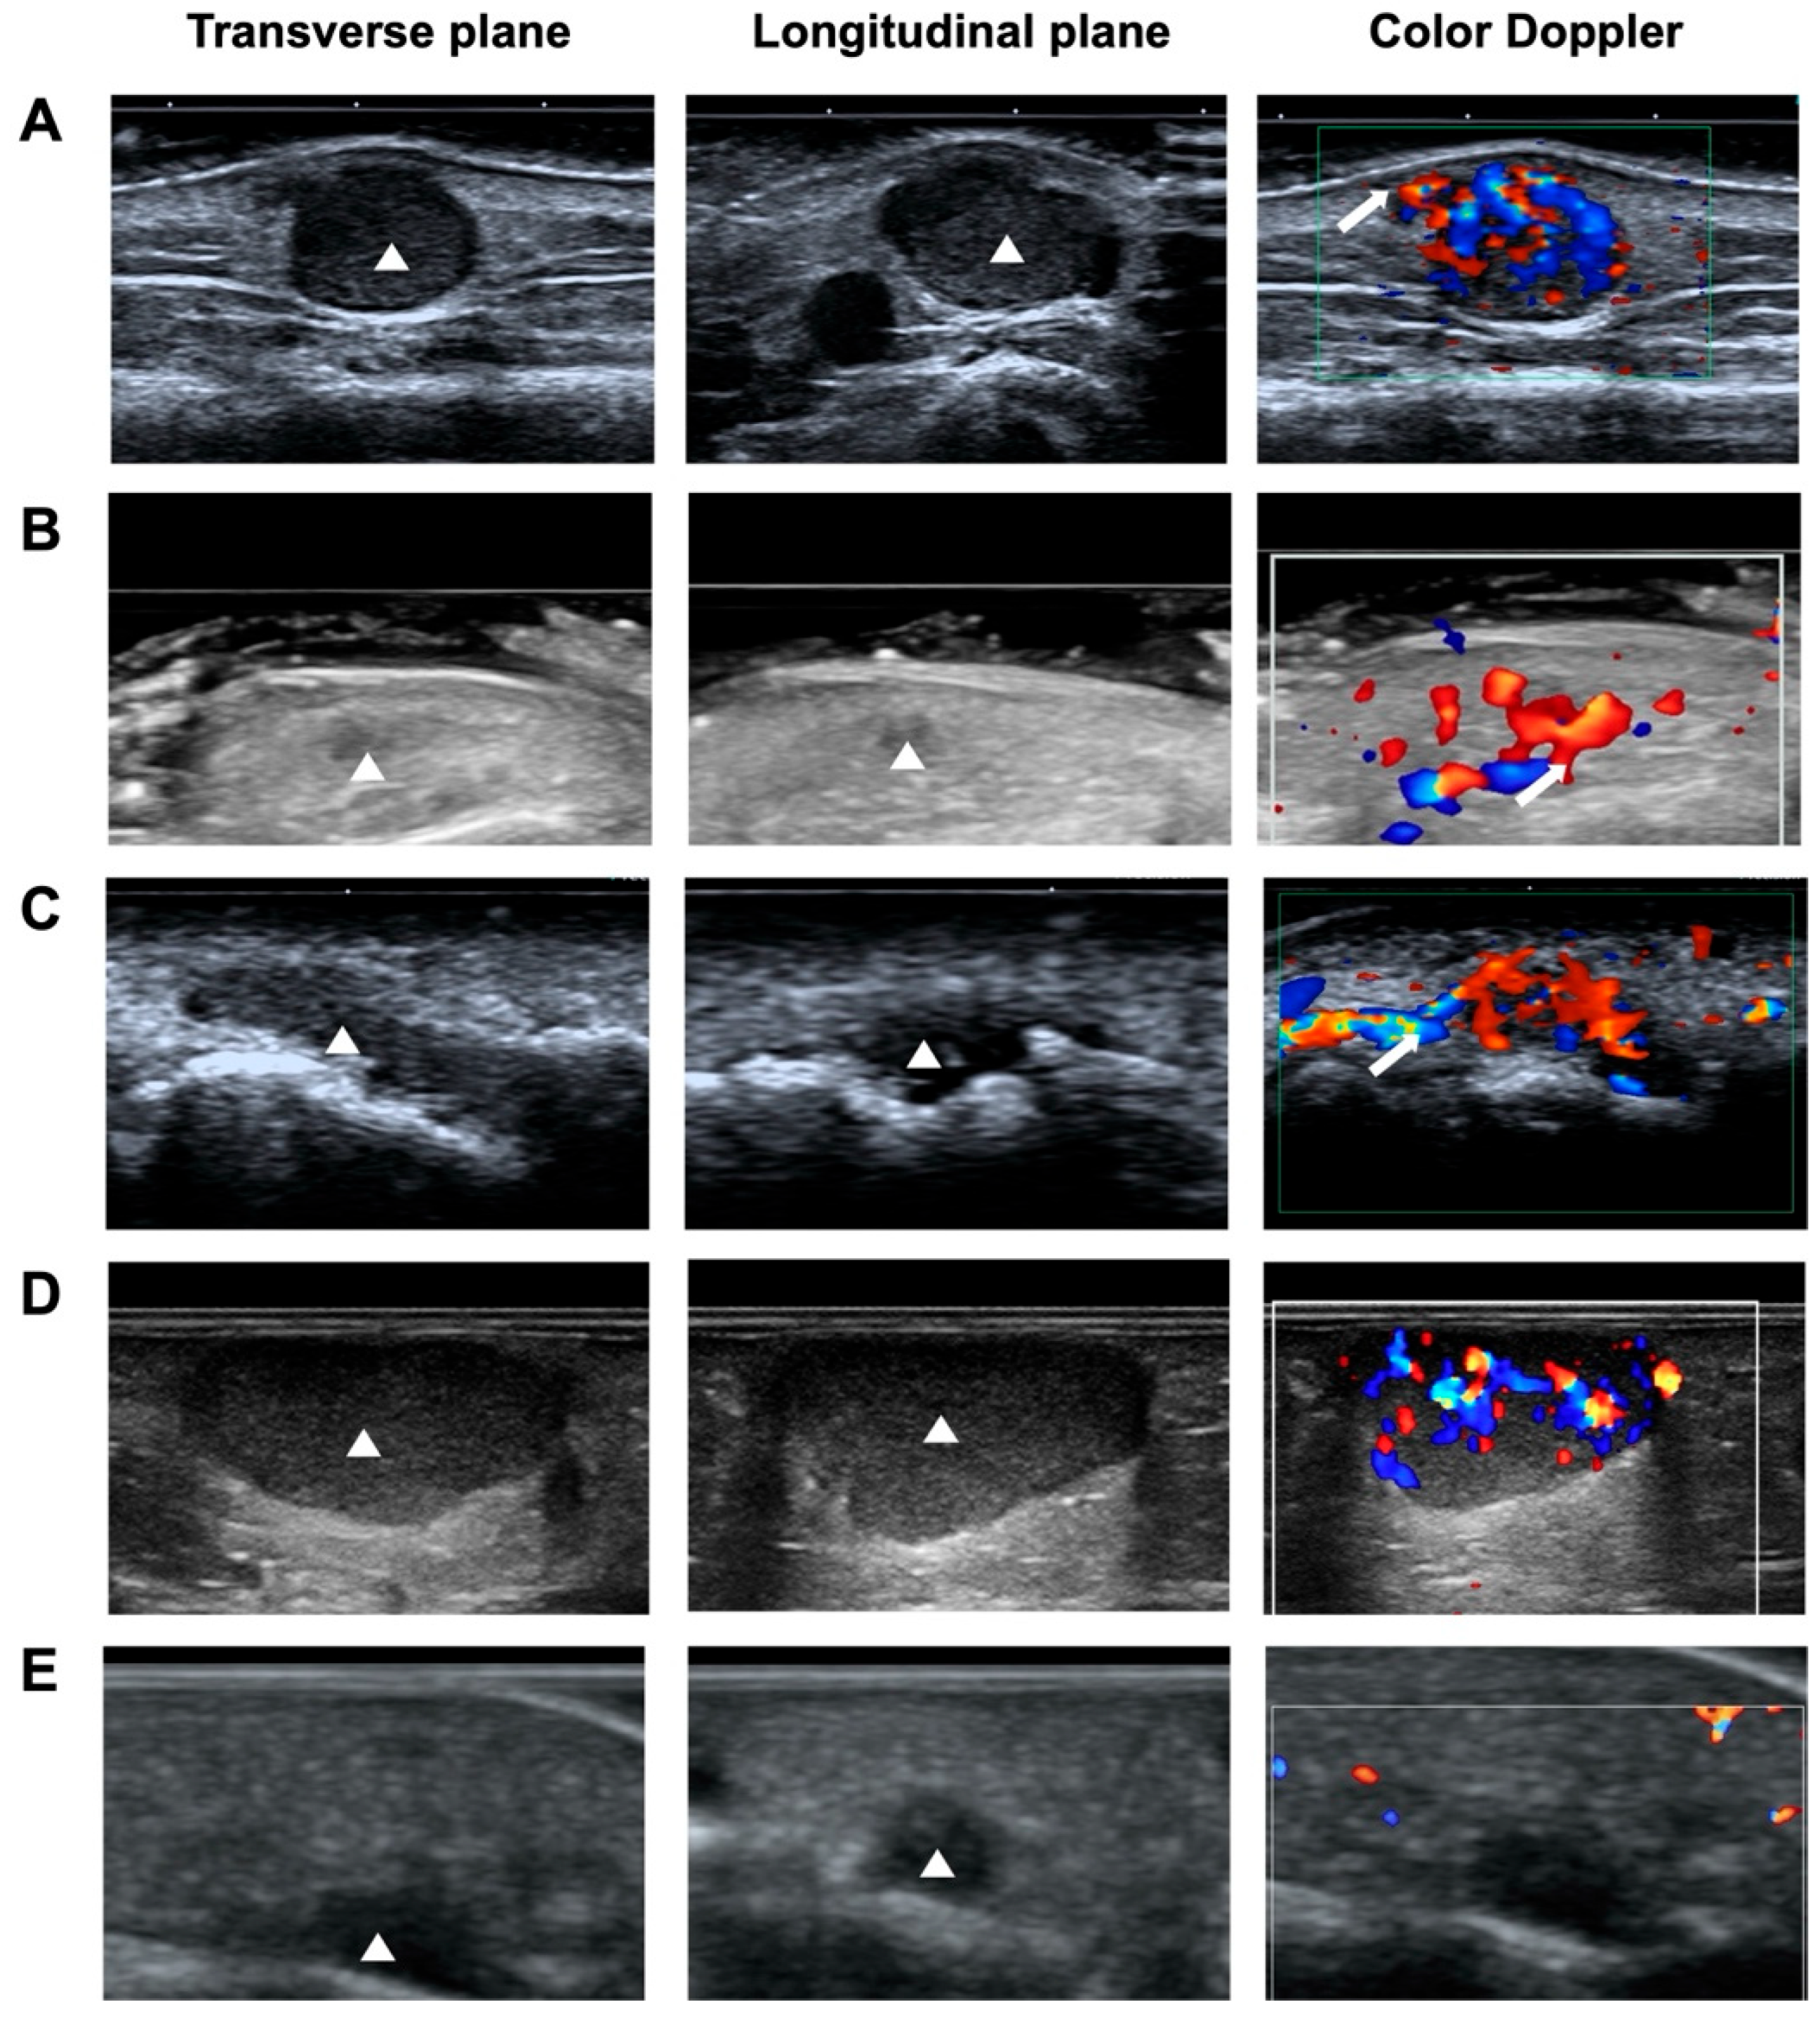

The sonographic features of NSGTs, ALMs, and hemangiomas were summarized in Table 2 and representative sonograms of the three types of diseased were shown in Figure 1. Most of NSGTs (75.86%) and ALMs (94.12%) presented an oval shape. Comparably, 49.25% of hemangiomas presented as irregular, significantly higher than their NSGT and ALM counterparts (p < 0.001). Nearly all the three types of tumors were horizontally orientated, with only one NSGT and one ALM in vertical orientation.

3.4.4. Vascularity

The blood vessel patterns observed by color Doppler ultrasound of these three types of superficial soft tumors could present as no, minimal, moderate, and marked blood-flow signals, with no significant differences (p > 0.05). Interestingly, as reported by Hee-Jin Park et al. [22], vascular stalk sign, reflecting the vascular origin of the tumor (Figure 1A), was observed in 38 NSGT patients (65.52%), significantly higher than that in ALMs (27.94%, p < 0.001) and hemangiomas (16.42%, p < 0.001).

Figure 1. Representative gray scale and color Doppler ultrasonograms of NSGT, ALM, and hemangioma. (A) Gray-scale ultrasound images obtained using high-frequency ultrasound show a hypoechoic mass measuring 7 × 3 mm in the subcutaneous tissue in the right arm of a 56-year-old man (yellow arrowhead). Color Doppler ultrasound reveals a hypervascular lesion (grade 3) with a vascular stalk sign (yellow arrow). (B) A hypoechoic mass measuring 15 × 6 mm in the left foot of a 31-year-old man (yellow arrowhead), with vascularity of grade 1. (C) A hypoechoic mass measuring 19 × 6 mm on the right finger of a 36-year-old woman (yellow arrowhead), with vascularity of grade 3.